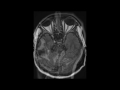

Transverse/Sigmoid Sinus Venous Thrombosis

This is a case of right-sided transverse, sigmoid, and jugular venous thrombosis presenting in a 66-year-old male with a history of pancreatic neuroendocrine neoplasm. On the axial T2-weighted image, there is increased T2 signal intensity in the distal transverse and proximal right sigmoid sinus on the right with additional increased T2 signal intensity at the proximal right internal jugular bulb. As we can see on the left, the normal appearance of the dural venous sinuses is hypointense on the T2-weighted sequences, due to the presence of venous flow. The second image, with FLAIR weighting, demonstrates increased FLAIR signal hyperintensity in the right transverse sinus. The third image, which is sagittal T1-weighted and off midline, demonstrates hyperintense signal compatible with thrombus extending from the right jugular bulb more inferiorly. The findings are confirmed on the DWI and ADC map, images four and five, where there is diffusion restriction at the sites of thrombosis. The 3D maxim intensity projection MR venogram confirms absence of flow within the thrombosed transverse sinus, sigmoid sinus, and internal jugular vein on the right. Causes of venous sinus thrombosis include: acute dehydration, chemotherapeutic agents, hypercoagulable states, iatrogenic causes, infection, malignancy as in our case, malnutrition, pregnancy, and trauma, among others.